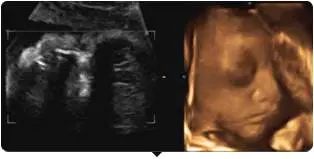

你可以通过美国GE-730高清四维彩超

看到胎宝宝最可爱撩人的画面——

揉眼睛